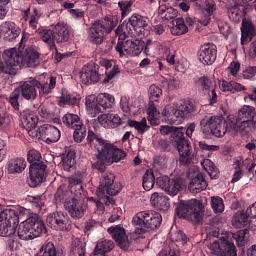

Setup. We evaluate all models on the Camelyon16 Whole Slide Image cancer detection dataset (Bejnordi et al., 2017). Each instance consists of a high resolution image of tissue from a medical scan which is pre-processed into patches of RGB pixels. After pre-processing, the average number of patches in a single set is over 9,300 (7.3GB), making each input roughly equivalent to processing 1% of ImageNet1k (Deng et al., 2009). The largest input in the training set contains 32,382 patches (25.4 GB). We utilize a ResNet18 (He et al., 2016) which is pretrained on Camelyon16 (Li et al., 2021) via SimCLR (Chen et al., 2020) as a backbone feature extractor whose weights can be downloaded from this repository111https://github.com/binli123/dsmil-wsi. Our goal is to first pretrain MBC set encoders on the extracted features, and then use the unbiased estimation of the full set gradient to fine-tune the feature extractor on the full input sets. We evaluate the performance of UMBC against non-MBC MIL baselines: DS-MIL (Li et al., 2021) and AB-MIL (Ilse et al., 2018), as well as MBC baselines: DeepSets and SSE.

The Camelyon16 Whole Slide Image dataset consists of 270 training instances and 129 validation instances. The dataset was created for a competition, and therefore the test set is hidden. We therefore follow the example set by previous works (Li et al., 2021) and report performance achieved on the validation set. For preprocessing, we consider the slide magnification setting, and use OTSU’s thresholding method to detect regions containing tissue within the WSI. We then split the activated regions into non overlapping patches of size . An example of single input patches can be seen in Figure 12. The largest input set contains image patches which are each . All patch extraction code can be found in the supplementary file. Table 14 contains statistics related to the numbers of patches per input for the training and the test set as well as the distribution of positive and negative labels.